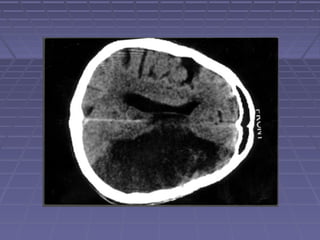

 TAC de cráneoTAC de cráneo si: persisten o aumentan lassi: persisten o aumentan las

manifestaciones clínicas, se sospechamanifestaciones clínicas, se sospecha

herniación, persiste la fiebre.herniación, persiste la fiebre.

 TC: hidrocefalia, lesiones vasculares,TC: hidrocefalia, lesiones vasculares,

tuberculomastuberculomas